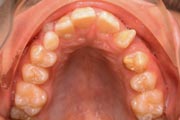

Crowding

Before